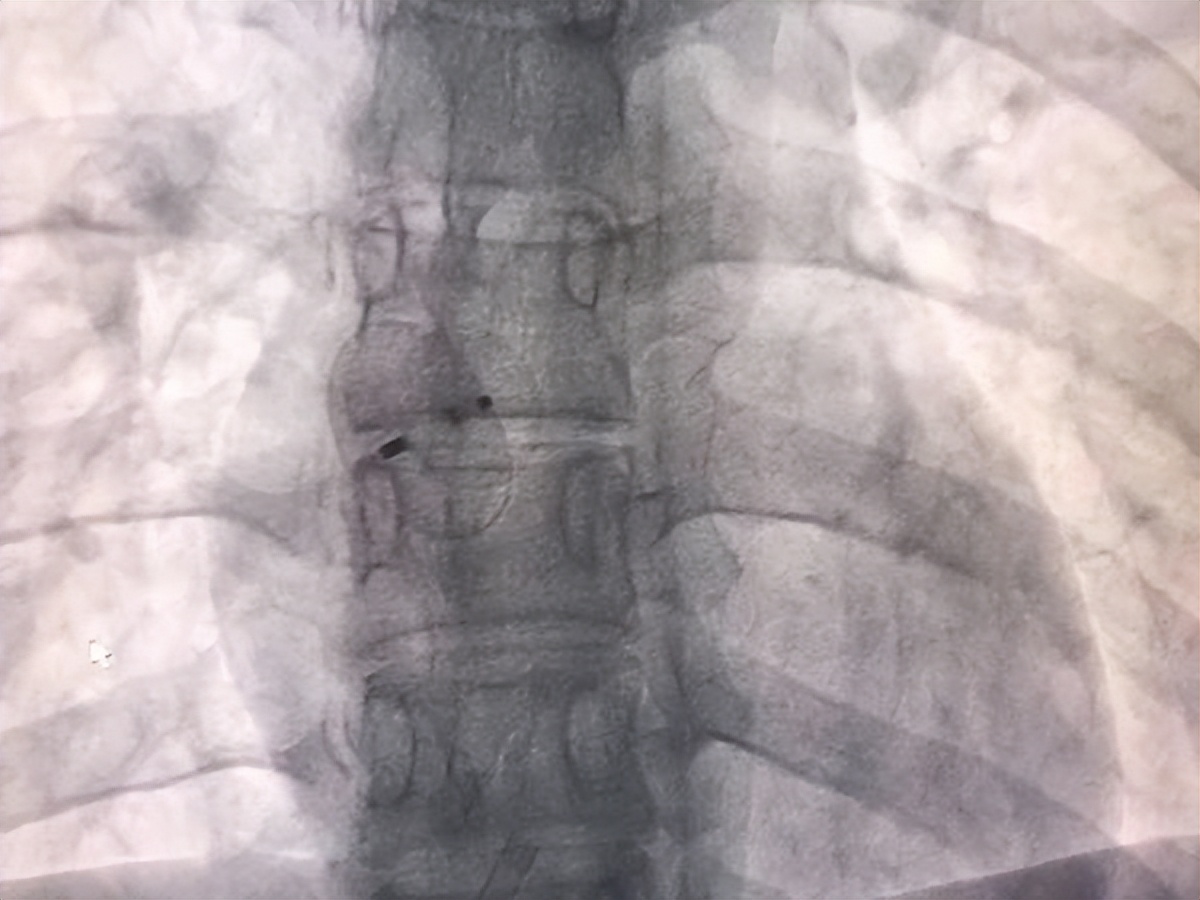

8月9日,在汝州市人民医院心血管内科二病区与介入导管室通力合作下,成功为其进行卵圆孔未闭介入封堵手术,手术过程顺利。“以后再也没有头痛生活的困扰了,感谢医院的医生们!解决了我多年的困扰!”小张感激地说道。术后小张恢复良好,头晕、头痛等症状得到了明显改善。